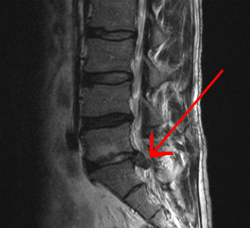

흡연자가 비흡연자에 비해 만성요통을 겪을 가능성이 3배나 높다는 연구결과가 나왔다.

페트레 박사의 연구팀은 요통을 처음 겪은 성인 환자 160명과 만성요통 환자 32명, 그리고 건강에 문제가 없는 참가자 32명을 대상으로 1년간 두뇌의 자기공명영상(MRI) 촬영을 했다. MRI 촬영 이후에는 요통의 정도 평가와 흡연 상태 및 건강에 대한 설문조사가 이뤄졌다.